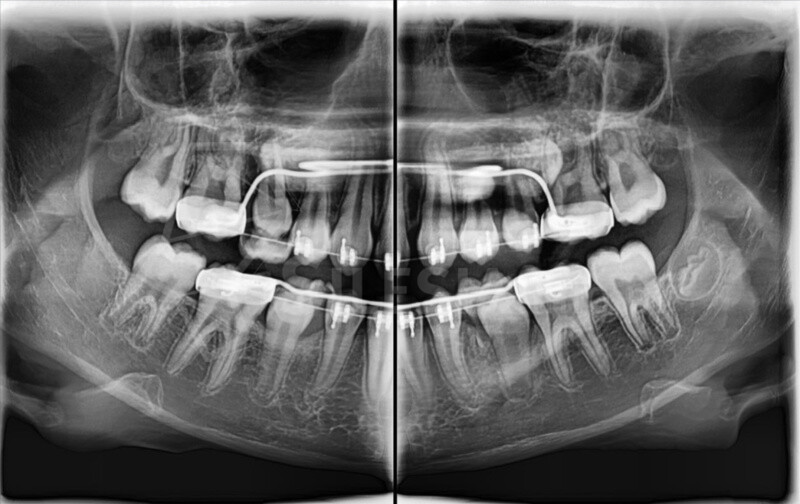

Zdjęcie panoramiczne (pantomogram) obejmuje całe uzębienie i szczęki, pokazując zmiany, których nie widać na zdjęciach punktowych RTG – takie jak torbiele, guzy, stany zapalne czy zwyrodnienia stawów.

Pracownia wyposażona jest w tomograf stożkowy Vatech Green X (model 2025) – najnowszej generacji urządzenie, które łączy najwyższą jakość obrazów 2D i 3D z minimalną dawkąpromieniowania.

Skanowanie trwa zaledwie 2,9 sekundy, a technologia AI automatycznie redukuje zakłócenia i poprawia ostrość zdjęć.